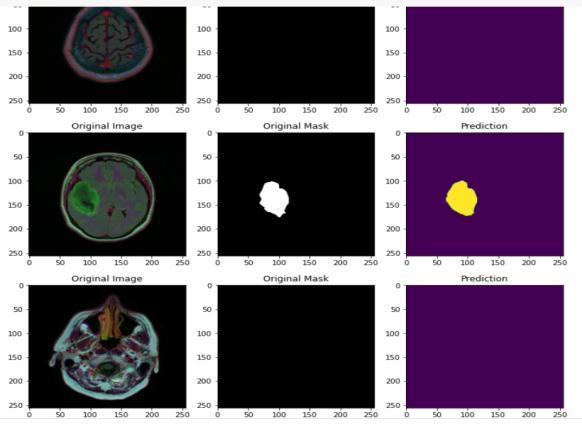

Fig.4.1.3Predictionformediumdataset

Fig.4.1.4Predictionforsmalldataset

4.1.1. Experimentation Dataset

The small dataset consisted of 250 images with 155 that showed the presence of tumor and 98 that did not show anytumor.Forthemediumdatasetweconsideredaround 4000imageswith2556imagesthathadtumorsand1373 thatdidnotshowanytumor.

Fig.4.4.3.PredictedOutput

We use three separate segmentation tasks to show the u net in action. The segmentation of neural structures in recordings made using an electron microscope is the first challenge. We employed a brain tumor segment dataset for this experiment, which is accessible online. 3064 MRI scans and 3064 masks are included. A collection of 30 images serially sized 512x512 section which transmits throughelectronmicroscopyoftheventralnervecordofa Drosophila serves as the training data (VNC). To proceed with the implementation and classification, the ground truth data which is completely tagged for each image is consideredforthewhiteandbackmatteroftheimages.U netmodelhasbeenchosenfortheexperimentationasthis model does not need any further processing either before or after diagnosis which internally makes the model less pronefortheerrorsandaswellensurethatitoutperforms otherclassifierswhichmayneedtobetrainedwithstrong featuremapsaftercarefulprocessingofthedata.However theU netmodelalsosuffersawarpandrandomerror.